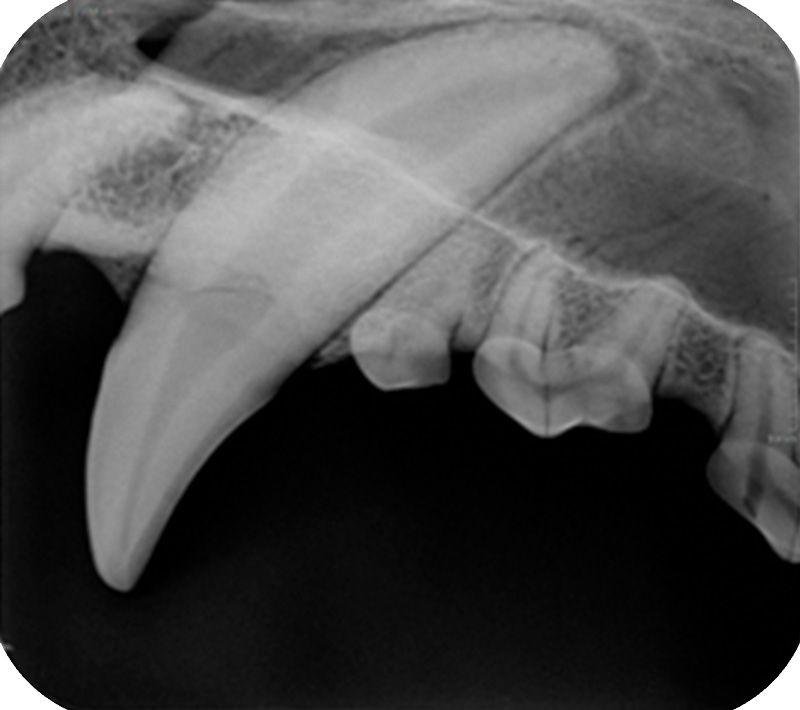

Der kompakte, benutzerfreundliche dentale CR Reader für schnelle und qualitativ hochwertige digitale Röntgenbilder – jetzt mit höherer Auflösung

Der einfach zu bedienende DigiVet® CR PLUS Dental Reader liefert jetzt eine noch brillantere Bildqualität. Mit einer Auflösung von 21 lp/mm lässt das digitale Speicherfoliensystem keine Wünsche mehr offen.